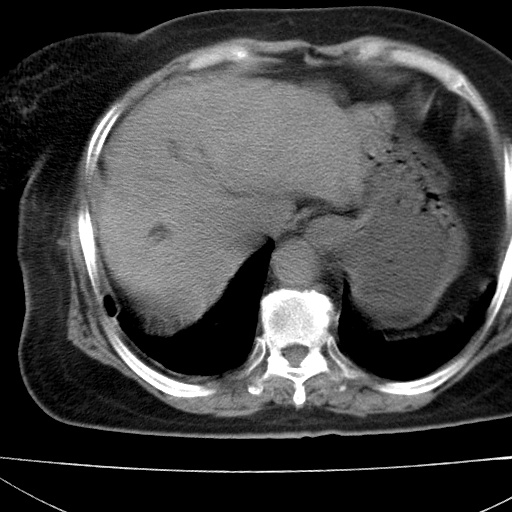

患者女74岁;右上腹胀痛1月,伴恶心,无发热;生活在疫水区。有术后病理及术后半年的追踪ct.

1)慢性血吸虫病(典型)。2)肝硬化。3)肝癌?4)胆囊炎。5)少量腹水。6)右侧少量胸腔积液。

支持.边缘见高密度线条样钙化影.

肝脏体积缩小,肝裂增宽,边缘不平呈波浪状,肝右叶见分隔状条索形钙化,亦见多结节低密度灶,边界不清,肝周可见少许液性暗区,胆囊增大内密度均匀,脾脏下缘低于脏脏的下缘,胸腔亦见液性暗区,余未见明显异常.

诊断:1肝硬化并慢性吸血虫病,脾肿大

2肝内占位,考虑肝癌可能性大,建议做增强

3胆囊炎, 4少量腹水及胸水

胆囊增大饱满,壁增厚。胆囊颈部见软组织密度影。临近肝右叶前段见片状低密度区,病灶下部见条状钙化,少量胸腹腔积液。意见:胆囊颈癌累及肝脏。

病人以胆囊癌手术的,病理结果为中分化腺癌。

现在看看肝右叶内圆形低密度影你们考虑什么呢?

肝内圆形低密度影考虑扩张的胆管

请看3mm重建像如下: